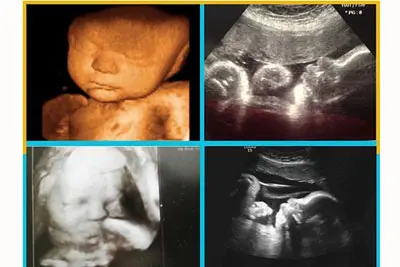

Ở tuần thứ 36 các chỉ số siêu âm của bé cũng gần như hoàn chỉnh, mà mẹ bầu cần chú ý, dưới đây là một số mức chỉ số an toàn:

- Đường kính lưỡi đỉnh BPD: 83-96mm, trung bình khoảng 90mm

- Chu vi vòng bụng AC: 285-375mm, trung bình khoảng 318mm

- Chiều dài xương đùi FL: 64-79mm, trung bình khoảng 70mm

- Chu vi vòng đầu HC: 309 - 352mm, trung bình khoảng 324mm

- Lượng nước ối có thể tăng lên khoảng 800ml hoặc nhiều hơn, mực nước ối khoảng 6-18cm, trong trường hợp thấp hơn hoặc cao hơn thì cần được theo dõi sát sao.